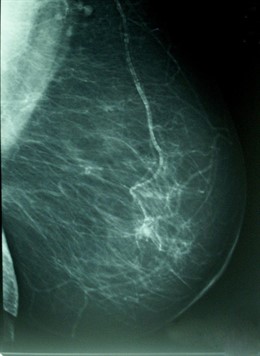

Los datos poblaciones, no obstante, señalan que la incidencia de este tipo de cáncer se estabilizó en el periodo 1993-2007, a la vez que se redujo la mortalidad en un 3,7% anual; mientras que en el periodo 2000-2004 aumentó la tasa de supervivencia más allá de los cinco años hasta el 84% de los casos, gracias especialmente al diagnóstico precoz, el cribado mediante la mamografía y a las mejoras en los tratamientos.

Según la Encuesta de Salud de Catalunya de 2011, el 91,2% de las mujeres entre 50 y 69 años se realiza una mamografía de forma periódica, un año en el que más de 386.000 mujeres se realizaron esta prueba clínica.

El programa de cribado del cáncer de mama puesto en marcha en Catalunya contempla un circuito de diagnóstico rápido, incluyendo a las mujeres de cualquier edad que presenten síntomas o molestias, y proporciona también consejo genético a personas con familiares cercanos que hayan desarrollado determinados tipos de cáncer.